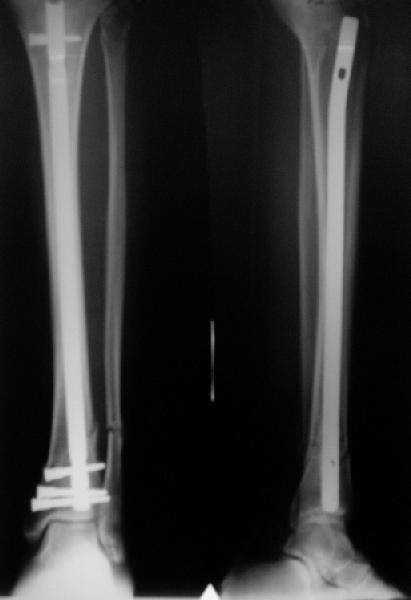

A typical case is attached, also an image with intra-op reduction obtained by a small wire distractor, in the moment of insertion a Poller wire in AP direction. Fixation by a SIGN nail. Despite the fibula was not fixed healing was obtained with the unchanged alignment.

There are some more tricks which allow not to plate the fibula and provide good alignment and stability. A small wire distractor can provide alignment and restore length of both tibia and

fibula. Angular stability of the tibia is provided by insertion of more than two conventional medial-lateral locking screws. To maintain the position of the fibula perQ insertion of a single position screw often could be enough. I bet the articles didn't analyze the options.

TDVC> little distal varus with some fibula distraction?

At least both the ankle mortise and tibial alignment look acceptable, don't they?

I am just trying to illustrate that prevention of 1)tibial valgus and 2)loss of reduction can be provided without fibular plating. Small changes of conventional nailing techniques allow to maintain reduction of the tibia reliably without adjunctive fibular stabilization.